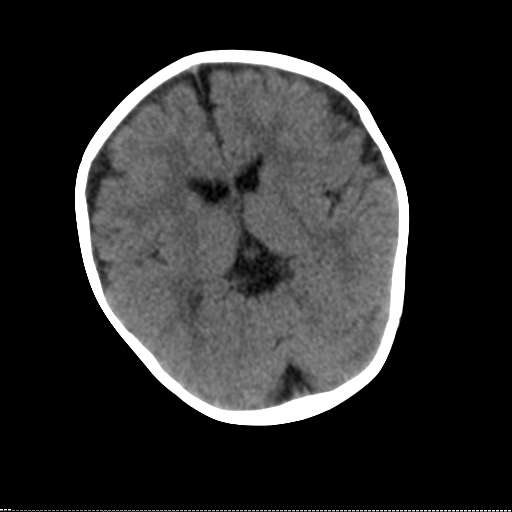

患儿 1岁 不能站立 出牙迟缓。反应尚可,临床怀疑脑发育不良。请各位专家指教。

小脑蚓部有没有问题?

先天性脑白质发育不良,mri明显

白质区相对少,可疑脑白质发育不良,建议做mri进一步检查。

沟裂较宽,脑回较粗,白质区减少,定期复查ct片或mri。